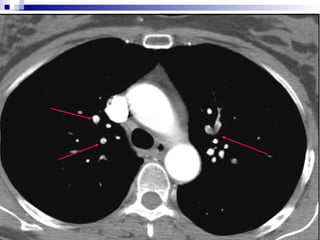

Spiral CT

• Direct visualization of emboli.

• Both parenchymal and mediastinal

structures can be evaluated.

• Offers differential diagnosis in 2/3 of cases